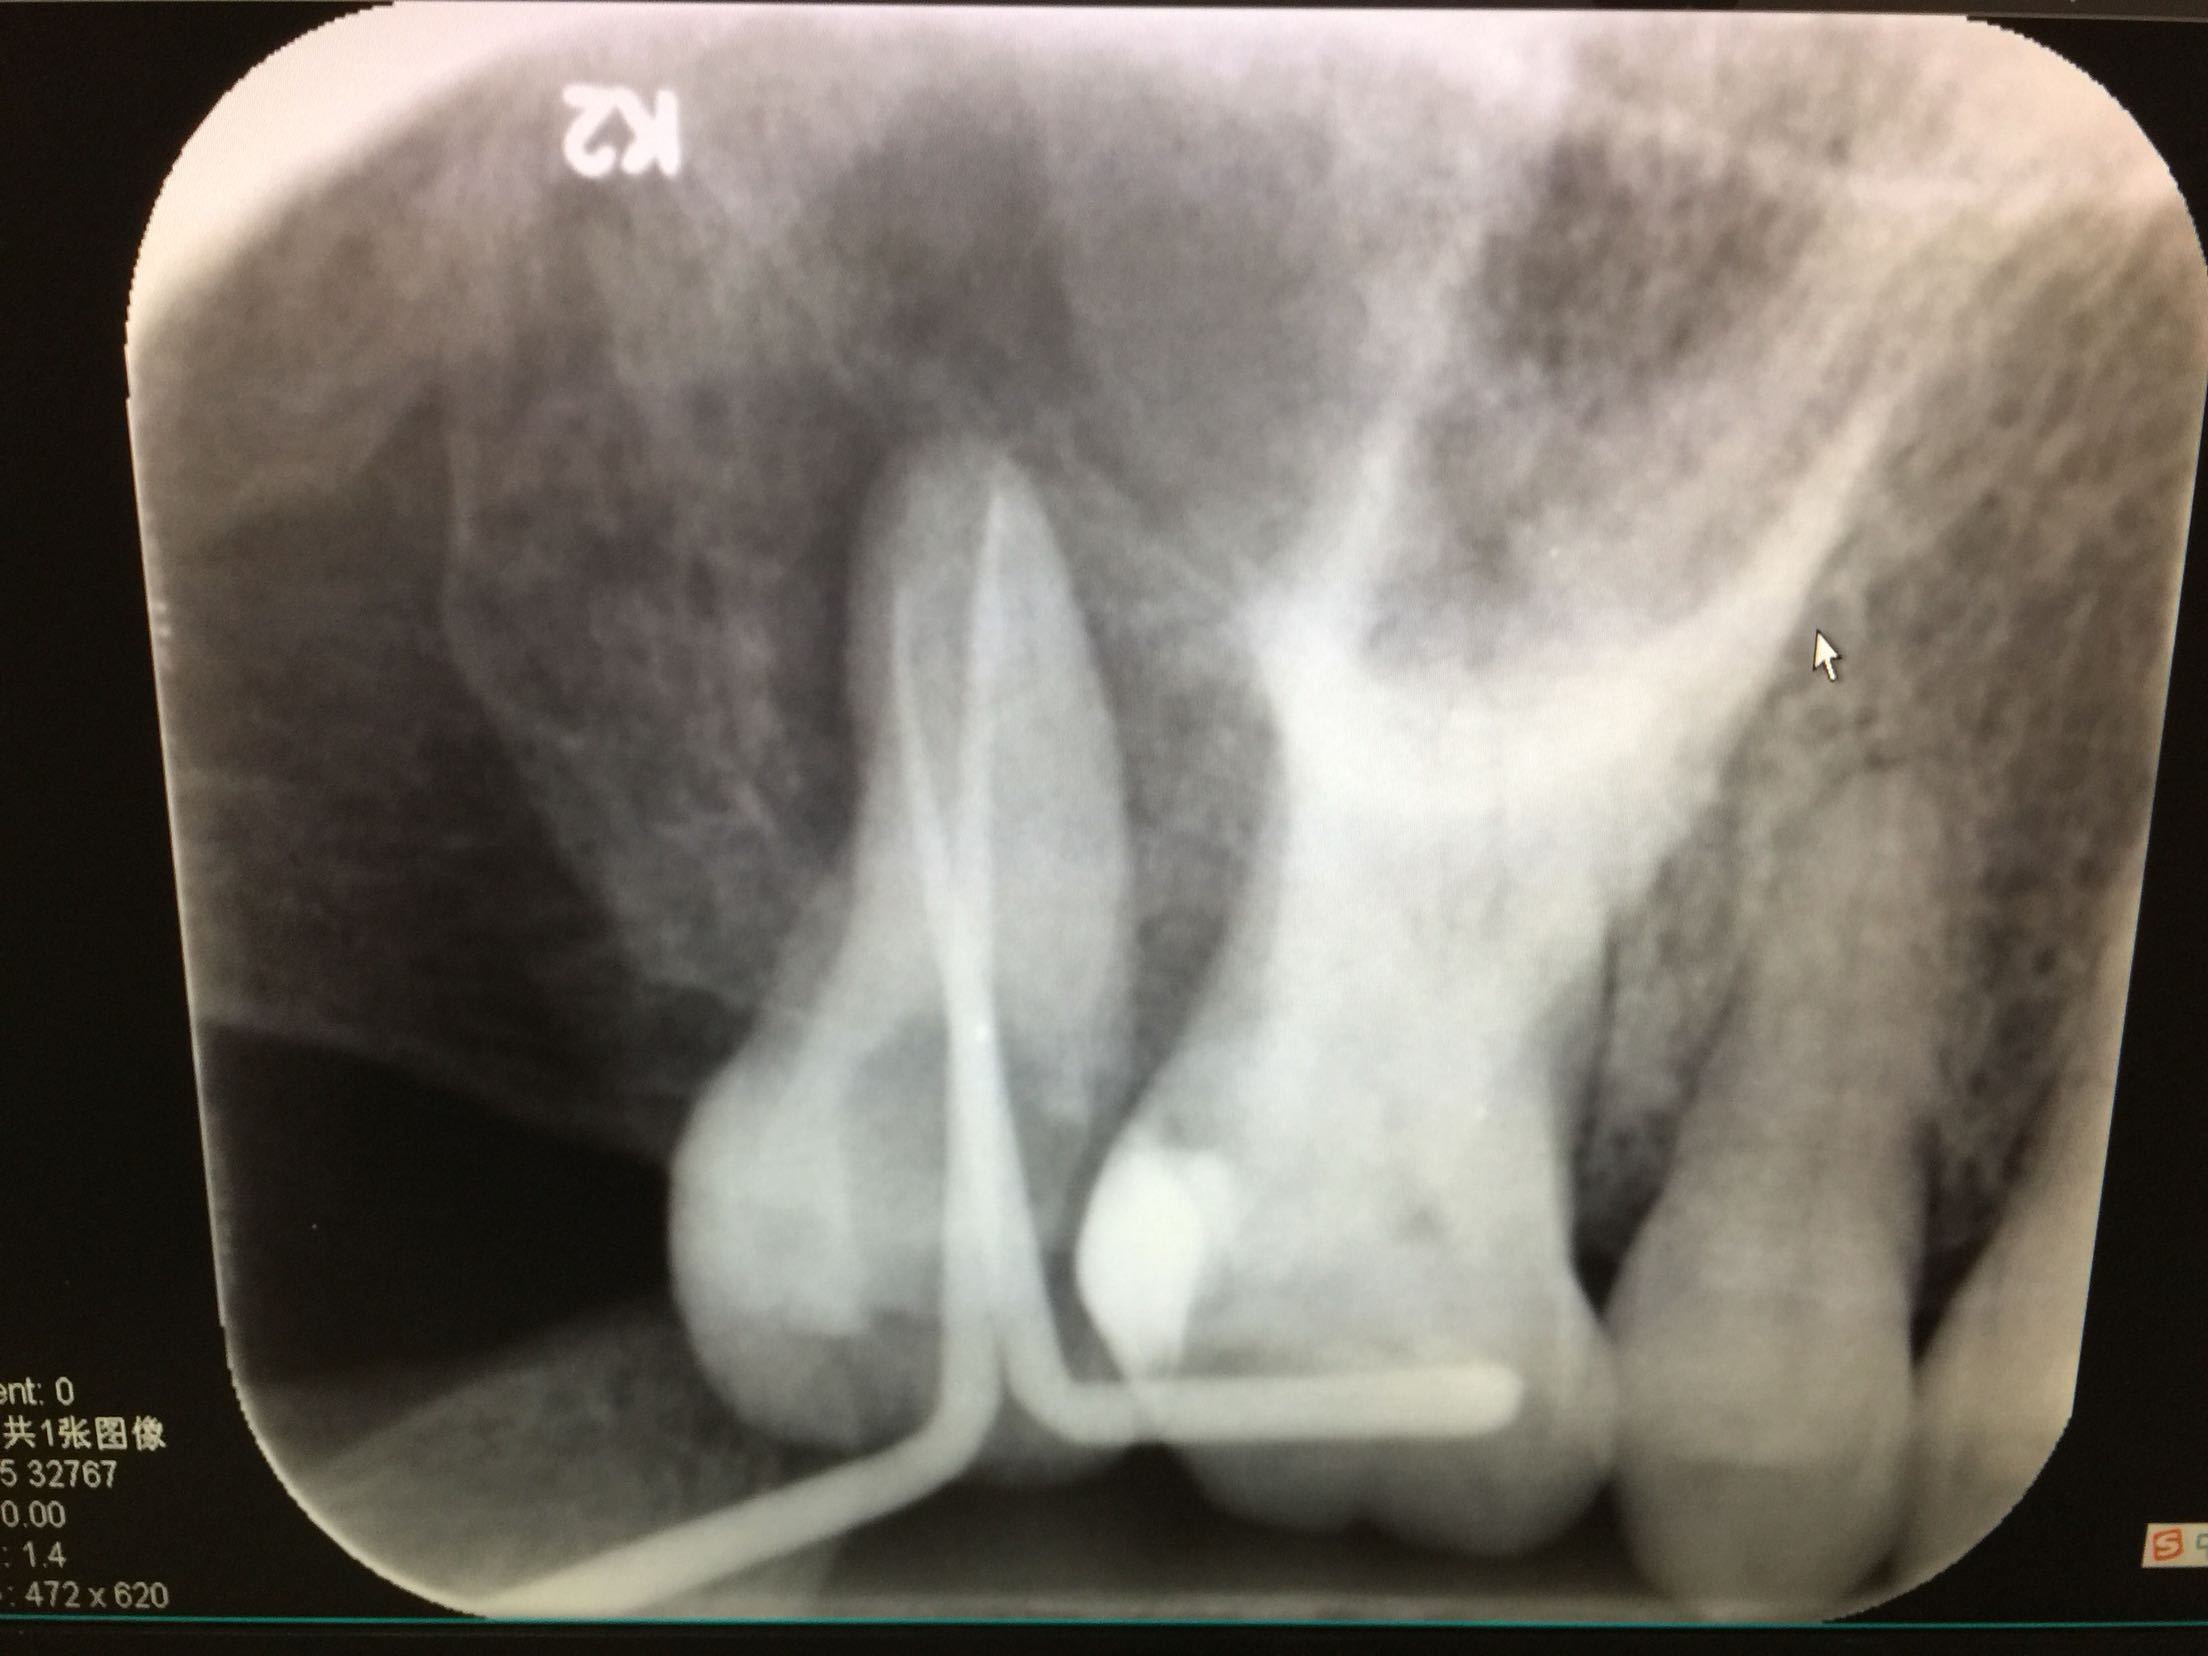

检查 17牙合面可见树脂补物,无继发龋。冷-,探-,叩++,不松。全口卫生差,全口牙龈不同程度退缩。 X线示:17牙已行根管治疗,根充不完善,很尖有暗影。

诊断:17牙根尖周炎 治疗计划:全口龈上龈下洁治术 17牙试行根管再治疗+冠保护 治疗. 17牙去除原补料,探查根管口,双根管,用氯仿溶解原牙胶,清扩,消毒,内封进口氢氧化钙,一周后复诊。 复诊. 诊间患牙疼痛消失,检查 冷-,探-,叩+-,不松。暂封完好,去除暂封,试主尖,合适,热充,回填。患者要求暂不行冠修复。已向患者交待不做冠保护可能会导致牙齿折裂等情况,患者知情同意。